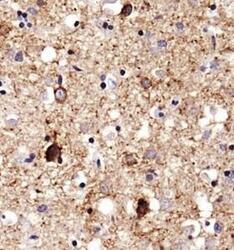

Supportive validation

- Submitted by

- LSBio (provider)

- Enhanced method

- Genetic validation

- Main image

- Experimental details

- Immunohistochemistry: SERF1A Antibody - Analysis of SERF1A in human Alzheimer's brain using DAB with hematoxylin counterstain. This image was taken for the unconjugated form of this product. Other forms have not been tested.